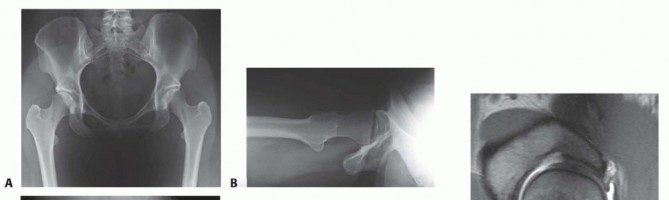

DEFINITION Varus intertrochanteric osteotomy involves the reorientation of the proximal femur in order to imp…